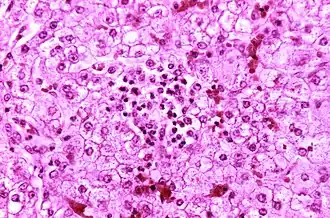

| Imagem microscópica do fígado de uma criança que morreu em consequência de síndrome de Reye. | |